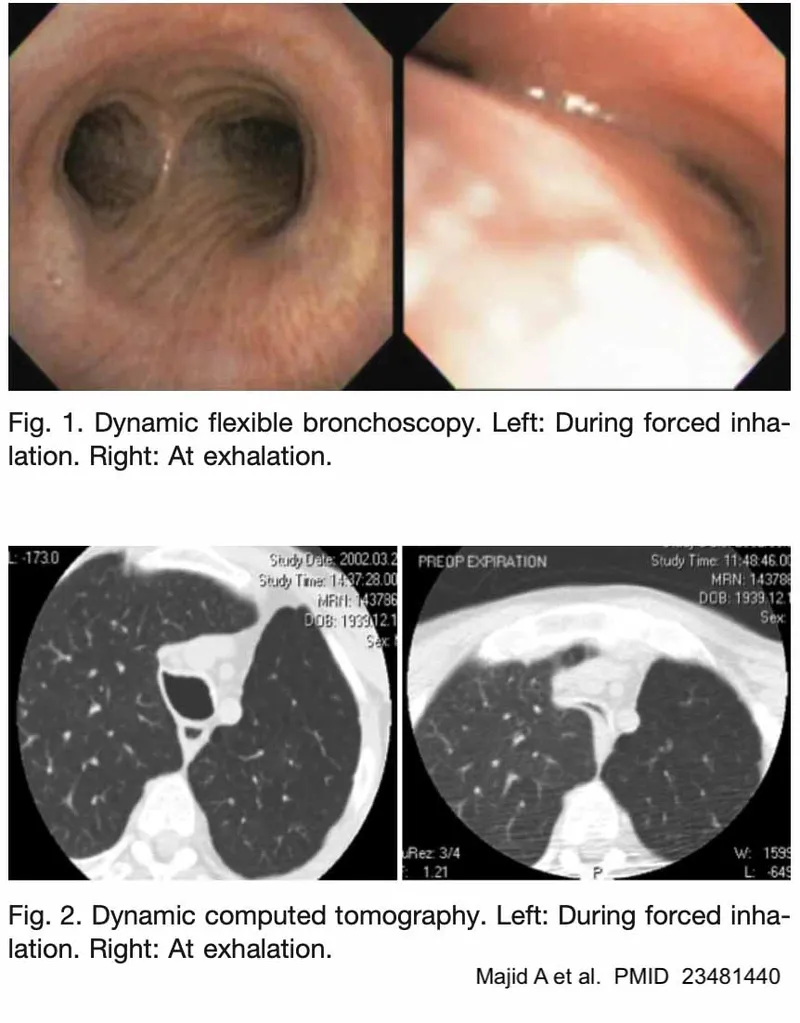

- Gold Standard: Flexible bronchoscopy (shows >50% luminal collapse during expiration).

- Fluoroscopy, CT/MRI (to identify extrinsic compression).